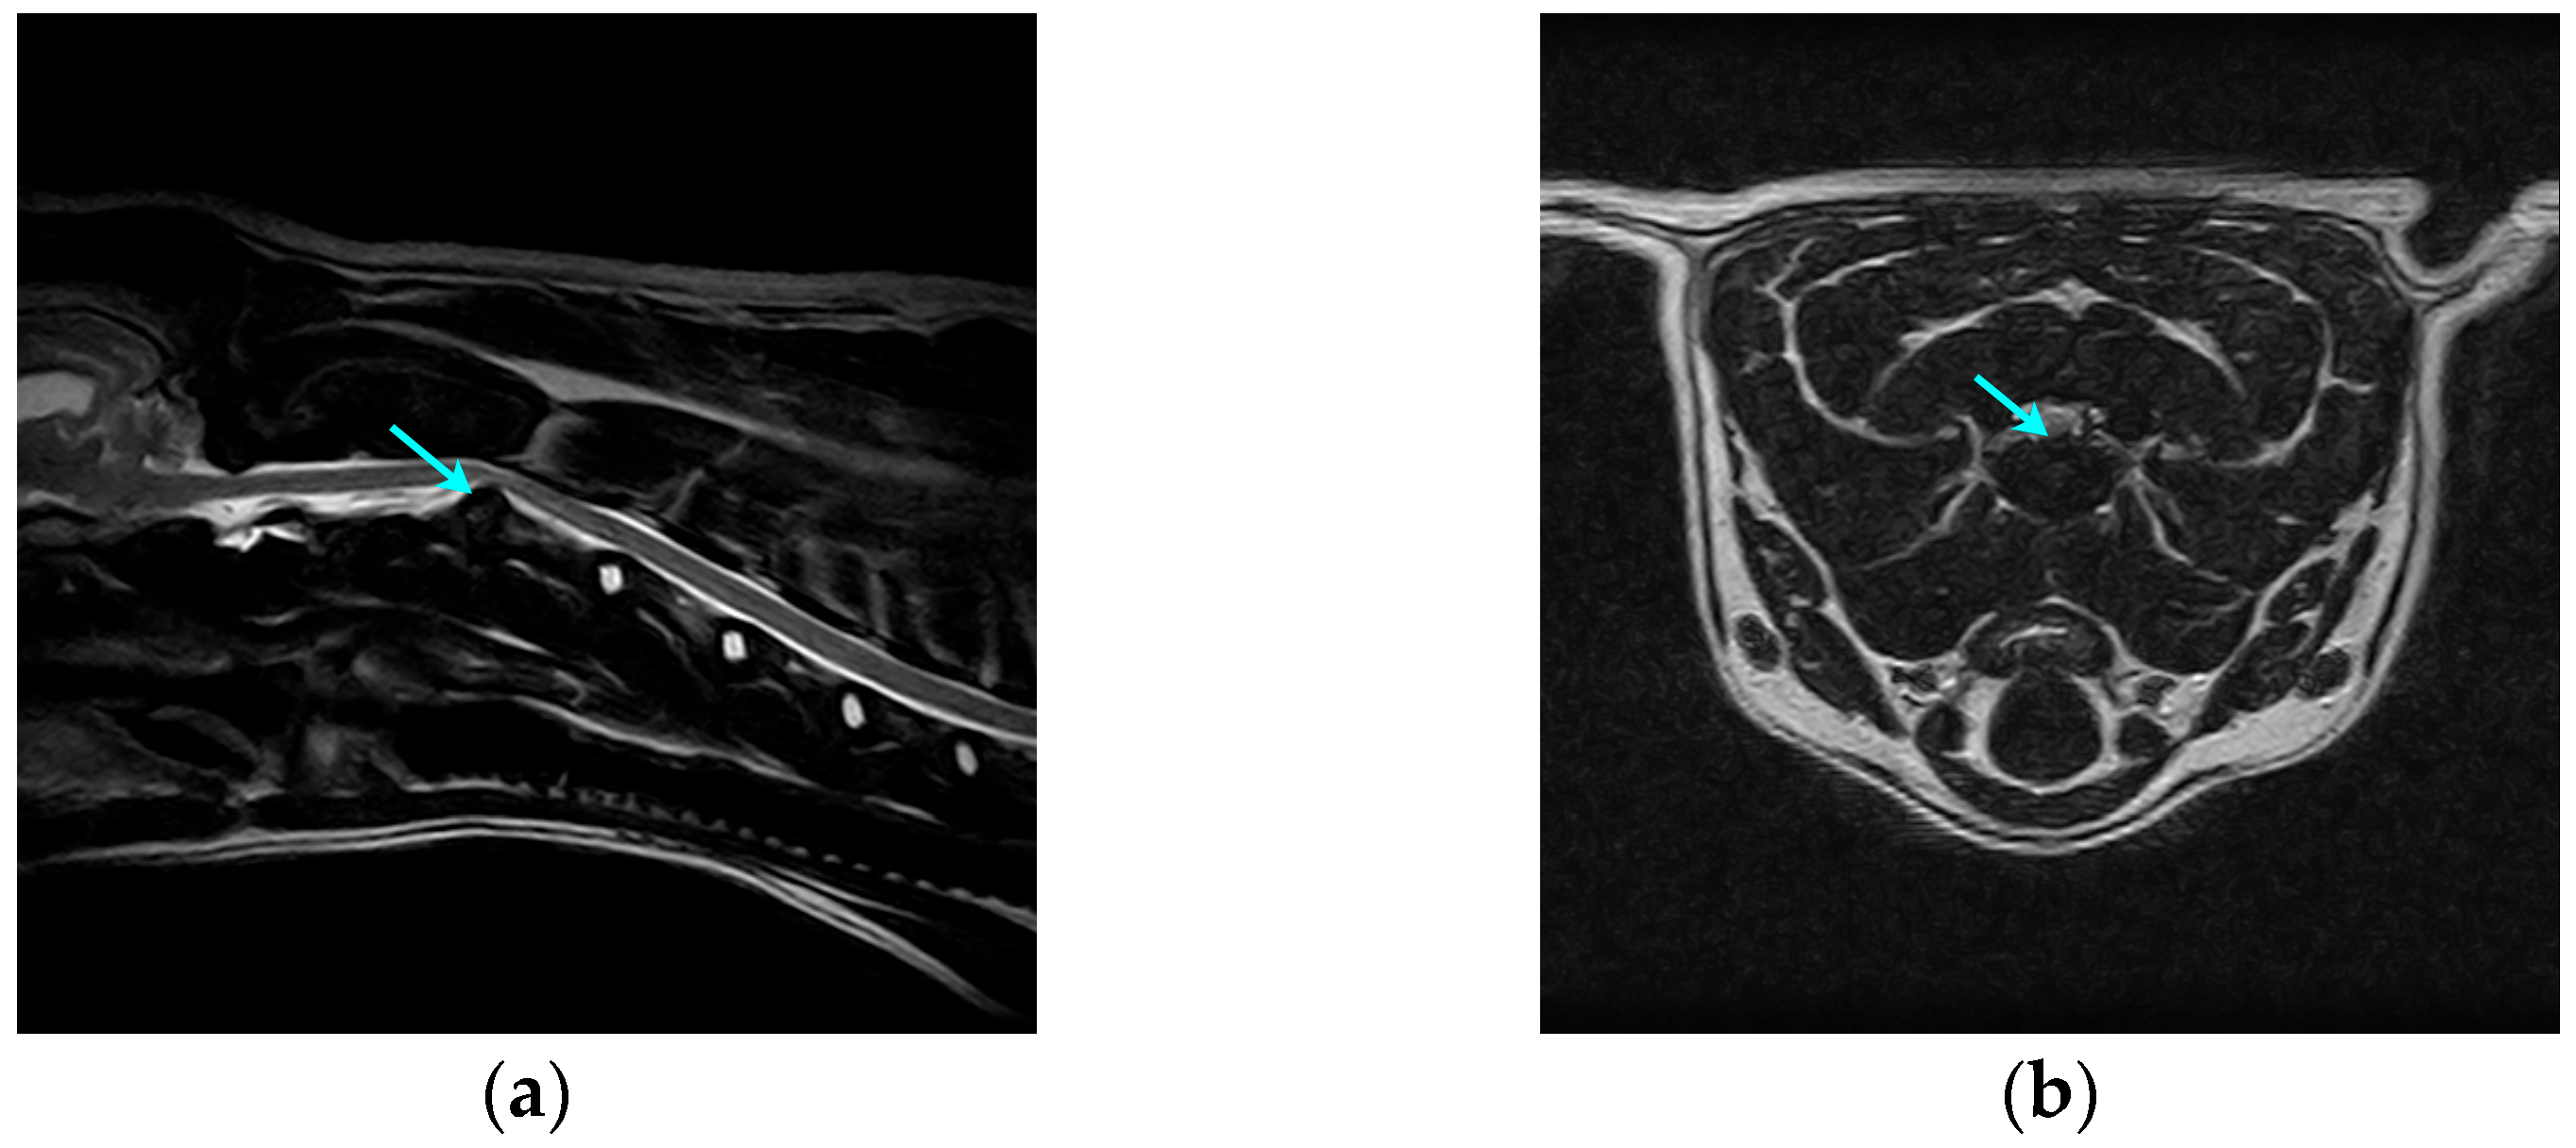

MRI was performed using a 0.35 T magnetic resonance imaging device (Spike Technology Development Co., Ltd., Beijing, China). The MRI protocols included T1WI, T2WI, and FS-T2WI, and left-sided sagittal and cross-sectional images of the C1-C7 segments were acquired (Figure 1), with an imaging layer thickness of 3 mm. The results were all interpreted by one senior veterinarian in the imaging department. The presence of an abnormal disc material signal with compression of the spinal cord or nerve roots was used as a diagnostic criterion.

Figure 1. Preoperative MRI images of a dog with cervical IVDH showing a C2-C3 disc herniation (arrows). (a) Left sagittal plane; (b) cross-section.